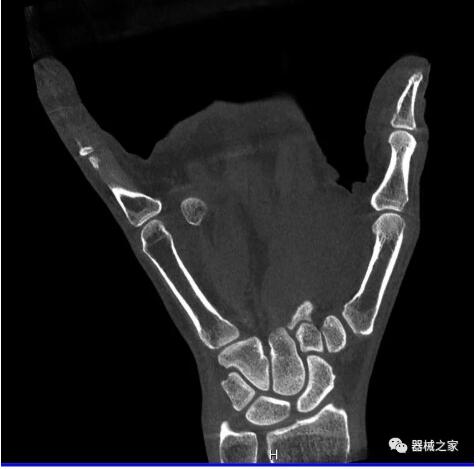

另外一款被稱為世界上最小的CT,它的重量僅300磅,不僅能夠掃查足部,還可以檢查膝蓋和上肢等。

與上面介紹的CT一樣,它同樣具有輻射低、占地空間?。?3*36)的特點,隨開隨用(支持直接接入墻上的插座)。

這款CT使用非常方便,通過上下移動保持與患者的手臂或者雙腿齊平,掃描快速,僅需要30秒左右就可以完成掃查。

以下是這些“特立獨行”的CT所拍出來的圖像: